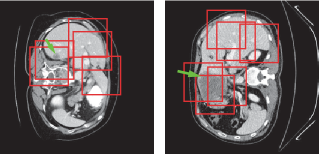

Refer to caption

Figure 6: Tumor patch extraction results. The green arrows point to the tumor regions and the red boxes show the patches used for training.